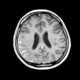

Carcinomatous infiltration

Leptomeningeal cancer (also called leptomeningeal carcinomatosis, leptomeningeal disease (LMD), leptomeningeal metastasis, neoplastic meningitis, meningeal metastasis and meningeal carcinomatosis) is a rare complication of cancer in which the disease spreads from the original tumor site to the meninges surrounding the brain and spinal cord. This leads to an inflammatory response, hence the alternative names neoplastic meningitis (NM), malignant meningitis, or carcinomatous meningitis. [Source: Wikipedia ]